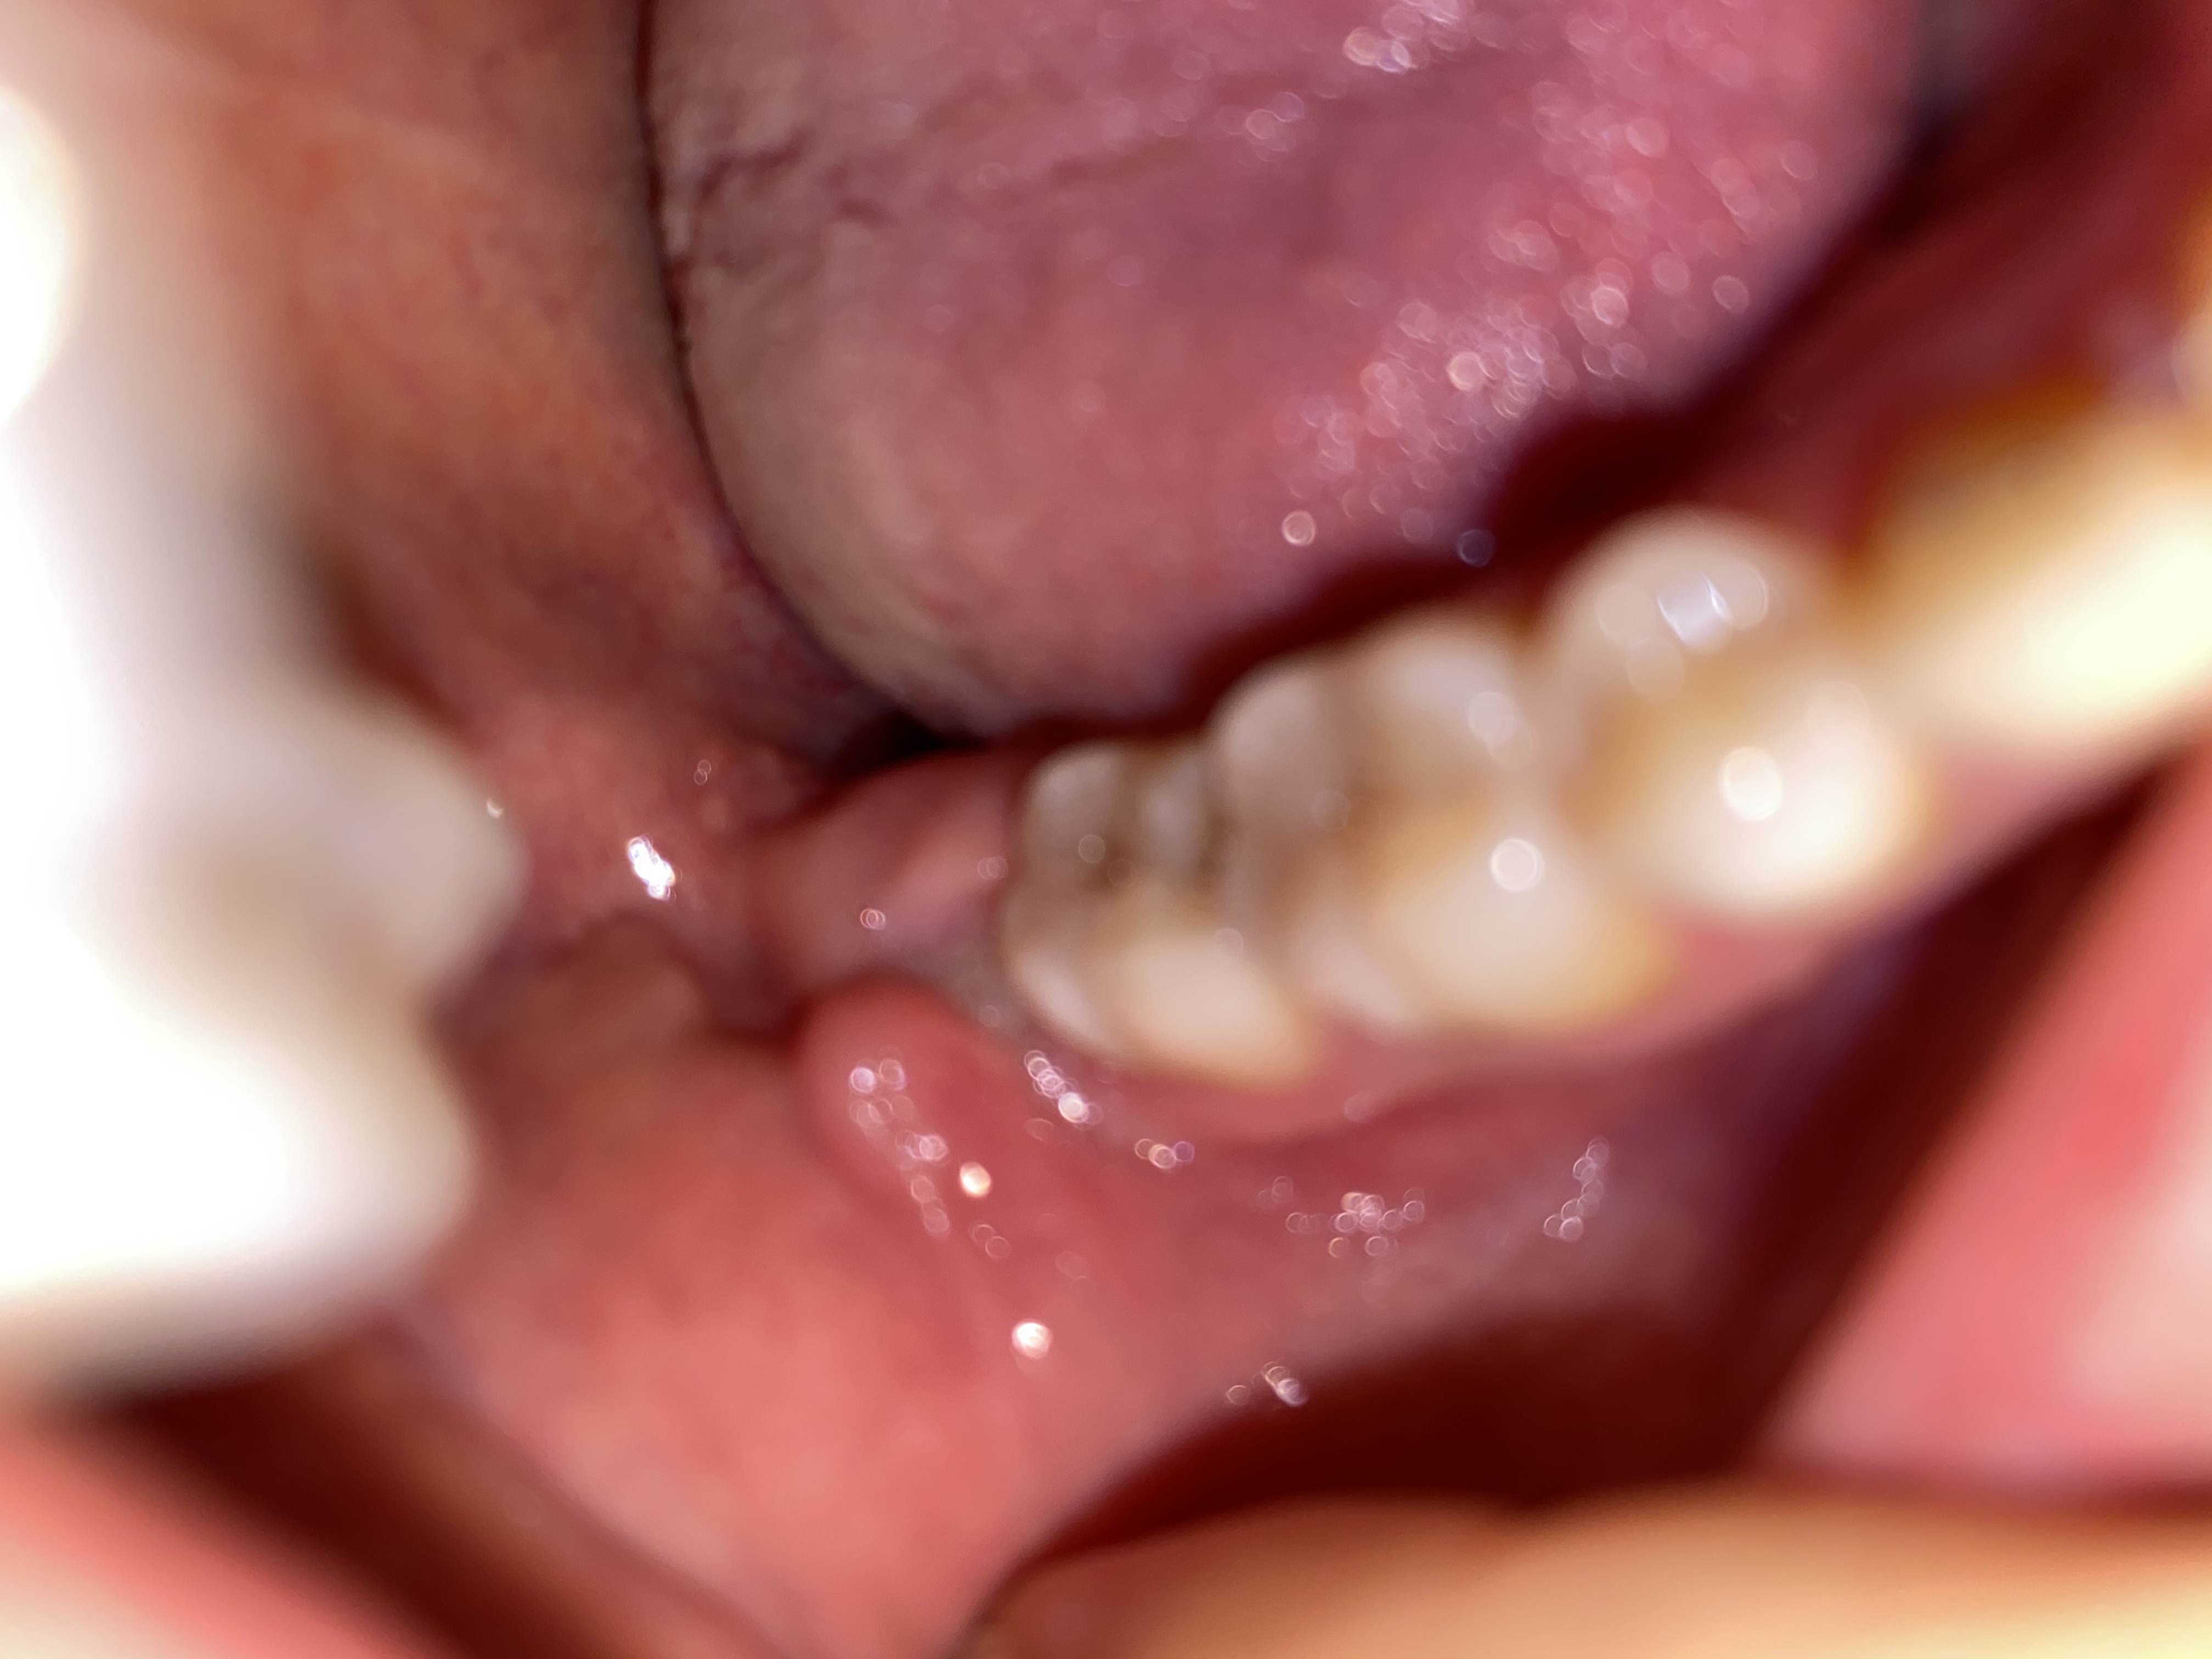

Buongiorno dottori, in attesa di una visita dal mio dentista volevo un vostro riscontro. Da qualche giorno il dente del giudizio è tornato a spingere per uscire, il dente non mi crea alcun fastidio l'unico dolore che ho è la guancia che internamente si è creato come un "salsicciotto" passatemi il termine, allego una fotografia. Cosa potrei fare per alleviare il dolore? Ho difficoltà anche a spazzolare i denti da quella parte. Grazie

Buongiorno, la sua situazione è una tipica pericoronarite, cioè un'infiammazione dei tessuti molli intorno al dente che molto probabilmente si trova anche in una posizione anomala (disodontiasi).

Sarà necessario valutarne estrazione dopo OPT (panoramica).